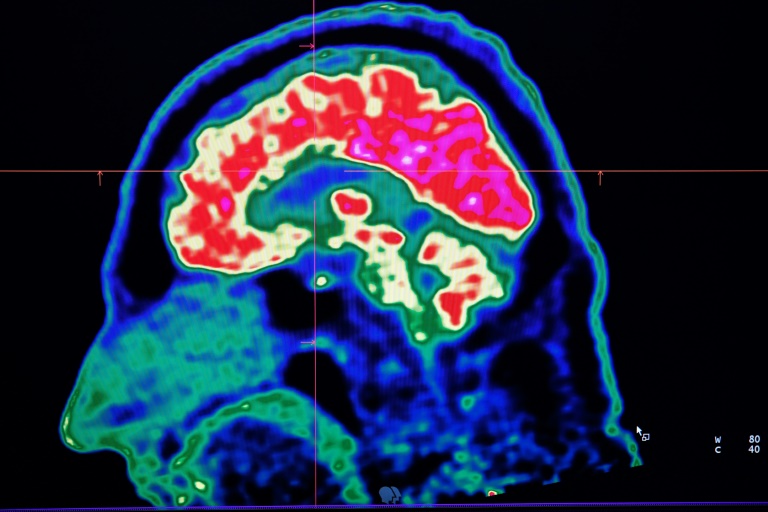

WASHINGTON - Conditions affecting the nervous system -- such as strokes, migraines and dementia -- have surged past heart disease to become the leading cause of ill health worldwide, a major new analysis said on Friday.

More than 3.4 billion people -- 43 percent of the global population -- experienced a neurological condition in 2021, far more than had previously been thought, the analysis found.

The researchers looked at how 37 different neurological conditions affected ill health, disability and premature death across 204 countries and territories from 1990 to 2021.